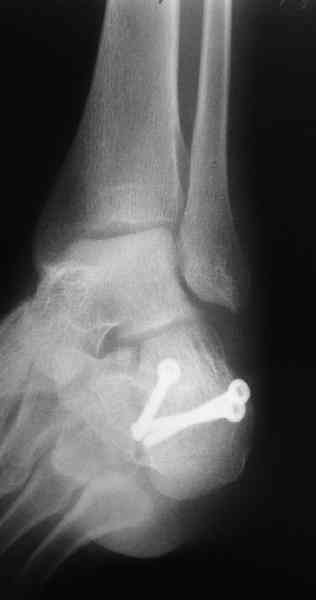

Какой предпочитаете доступ? Нет ли показательных рентгенснимков?

Открытый и закрытый способы лечения.